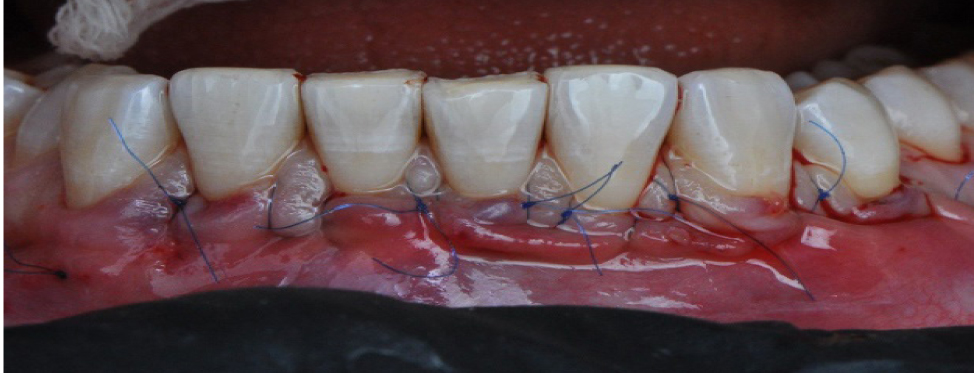

Вначале проводилась антисептическая обработка полости рта 0,05%-м раствором хлоргексидина биглюконата, аппликационная и инфильтрационная анестезии. Затем выполнялись разрезы в области десневой борозды (сулькулярные) через каждую зону рецессии микрохирургическим лезвием с сохранением кончиков десневых сосочков (рис. 2), отслаивание полнослойных лоскутов с помощью микрохирургического распатора. Далее производился забор свободного десневого трансплантата с неба с последующей его внеротовой деэпителизацией и наложением на зону забора параллельных и перекрестных горизонтальных обвивных швов (рис. 3). Позиционирование и фиксация трансплантата в принимающем ложе, ушивание раневой поверхности швами Аллена (рис. 4). Даны рекомендации по послеоперационному ведению: полоскания 0,05%-м раствором хлоргексидина биглюконата 2 раза в день в течение 2 недель, назначены противовоспалительные и обезболивающие лекарственные препараты (НПВС). Повторная явка через день. Швы снимались на 7–10-е сутки. Контрольные осмотры проводились через 3 и 6 месяцев, 1, 2 и 3 года соответственно, оценивалось состояние мягких тканей в области хирургического вмешательства и степень закрытия рецессий десневого края.

Рис. 4. Наложение швов Аллена